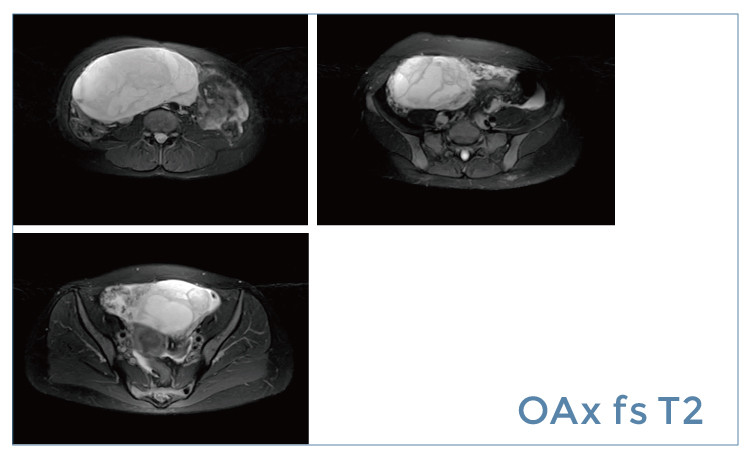

【朗润影像档案】磁共振影像病例分享(编号20190419)